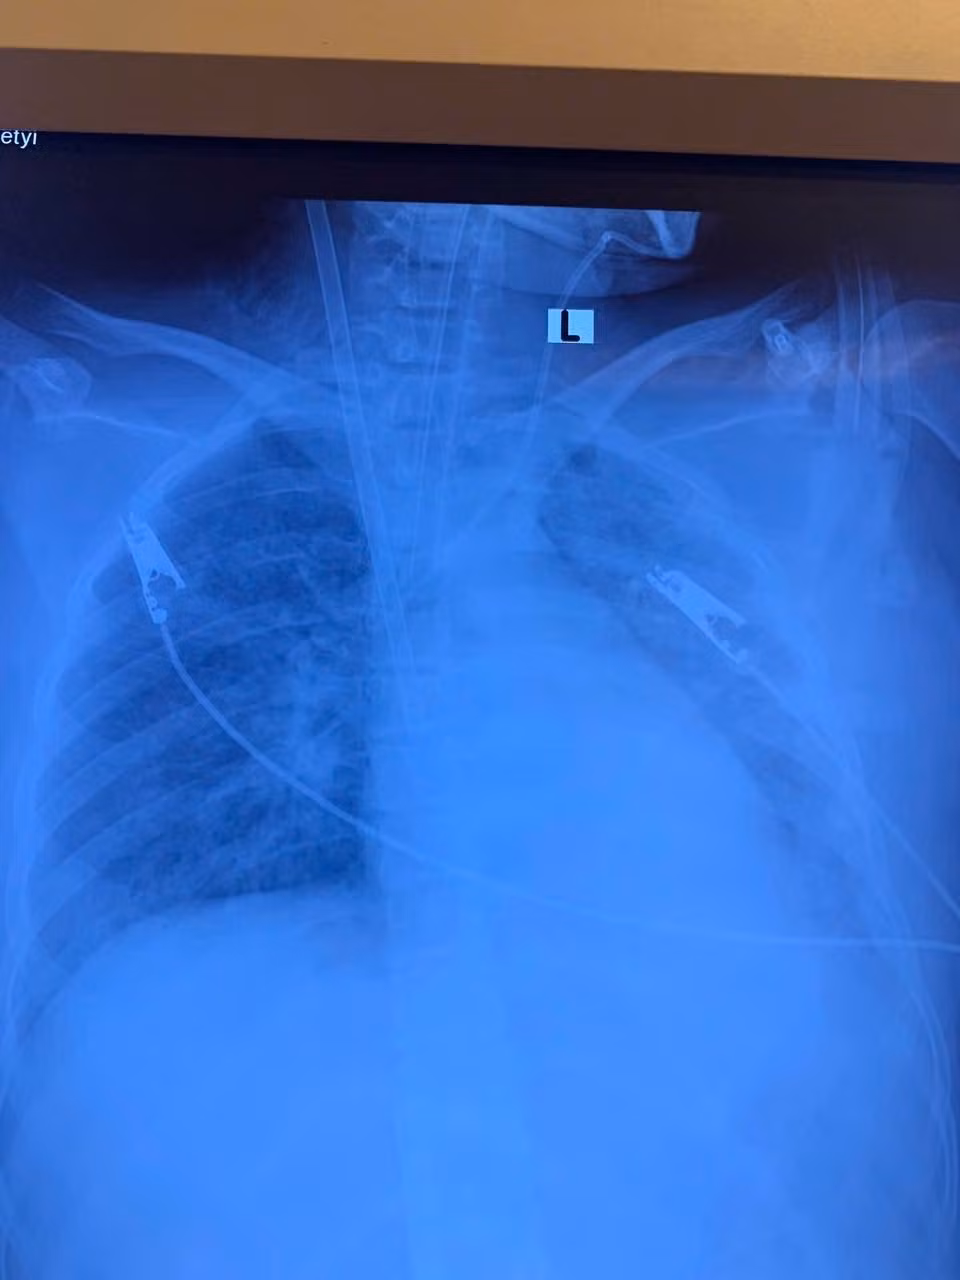

Phổi trắng xóa – hội chứng ARDS trên nền bệnh lý tiểu đường không được phát hiện

Bệnh nhân nữ, 19 tuổi, nhập viện trong tình trạng khó thở, sốt cao, ho đờm. Chẩn đoán ban đầu là viêm phổi nặng. Chỉ trong vòng 3 ngày, tình trạng hô hấp suy sụp nhanh chóng, hình ảnh X-quang và CT phổi cho thấy phổi trắng xóa hai bên – dấu hiệu điển hình của Hội chứng suy hô hấp cấp tiến triển (ARDS), một biến chứng nguy kịch thường gặp ở những ca viêm phổi nặng.

Hình ảnh tổn thương phổi trên phim chụp - Ảnh BVCC